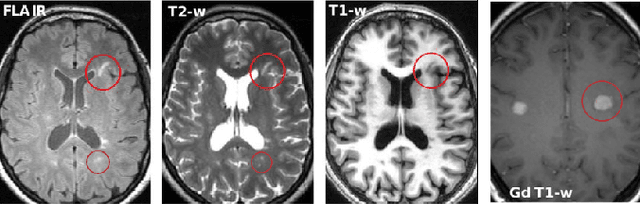

Abstract:Multiple sclerosis (MS) is a chronic inflammatory and degenerative disease of the central nervous system, characterized by the appearance of focal lesions in the white and gray matter that topographically correlate with an individual patient's neurological symptoms and signs. Magnetic resonance imaging (MRI) provides detailed in-vivo structural information, permitting the quantification and categorization of MS lesions that critically inform disease management. Traditionally, MS lesions have been manually annotated on 2D MRI slices, a process that is inefficient and prone to inter-/intra-observer errors. Recently, automated statistical imaging analysis techniques have been proposed to extract and segment MS lesions based on MRI voxel intensity. However, their effectiveness is limited by the heterogeneity of both MRI data acquisition techniques and the appearance of MS lesions. By learning complex lesion representations directly from images, deep learning techniques have achieved remarkable breakthroughs in the MS lesion segmentation task. Here, we provide a comprehensive review of state-of-the-art automatic statistical and deep-learning MS segmentation methods and discuss current and future clinical applications. Further, we review technical strategies, such as domain adaptation, to enhance MS lesion segmentation in real-world clinical settings.